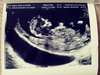

Nadrobie was wieczorem chce napisac ze jestem po usg i wszystko jest w porzadku, male skakalo ruszalo raczkami i nozkami , cudowny widok :) przyziernosc 1.7mm maluszek ma 6,3 cm termin sie przesnal z usg i jest na 14.12 takze dzidzi rosnie jak na drozdzach :) serduszko 170 uderzen no i na 90% chlopiec :D moj wymarzony hehe jestem przeszczesliwa.